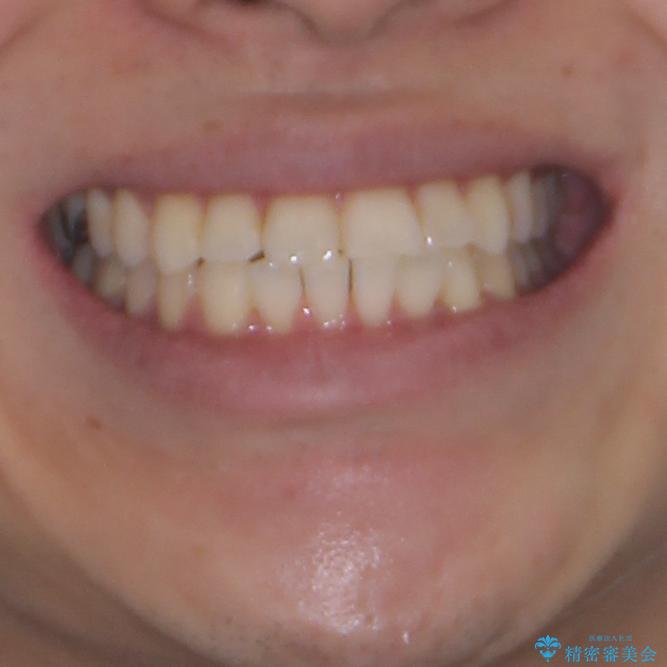

- 右下奥歯の虫歯がしみて痛いとのことで来院された患者様です。

虫歯が大きかったため、クラウンによる補綴治療が必要になる旨をお伝えしたところ、矯正治療にも興味があるとのことでした。

短期間で手間のかからない方法がご希望でしたので、ワイヤー装置による矯正治療を行うこととし、矯正治療後に右奥2歯をセラミッククラウンにて補綴することとしました。